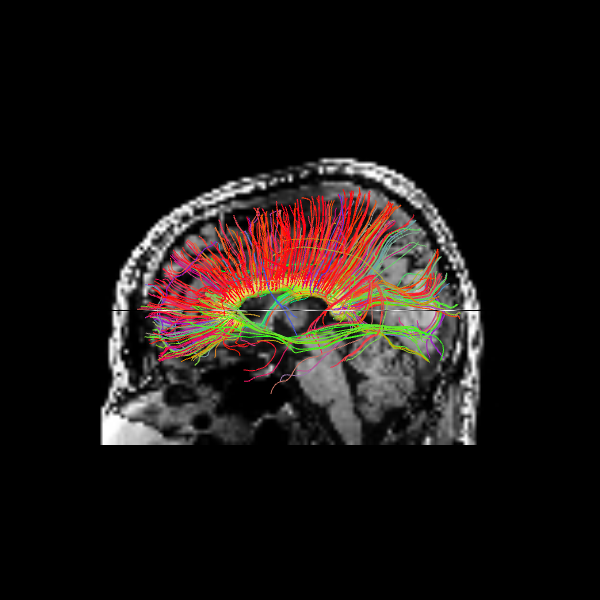

Since we seeded streamlines exclusively from the corpus callosum, all resulting fibers represent interhemispheric connections originating from this region. Let’s visualize them using probabilistic direction getter from SH (peaks_from_model):

Let’s visualize the Corpus Callosum using deterministic maximum direction getter:

The following alternative visualizations display the corpus callosum streamlines overlaid on T1-weighted anatomical slices (axial at z=35 and sagittal at z=35), with the seed ROI shown as a semi-transparent yellow contour.

The sagittal view illustrates these interhemispheric pathways connecting the two hemispheres.